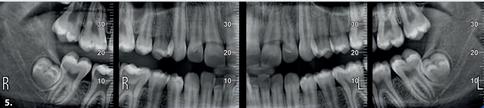

1 Orthogonal panoramic X-ray: minimises the overlapping of adjacent teeth and provides better periodontal analysis

2 Fast panoramic X-ray: low dose and reduced scan time, perfect for primary investigations, follow-ups or uncooperative patients

3 Child panoramic X-ray: limited exposure and optimised parameters for fast paediatric examinations.

4. Complete dentition divided into quadrants: localised investigations with selectable segmentation to limit the irradiated dose.

5. Bitewing projections limited to crowns: high resolution and low dose, a comfortable alternative to intraoral imaging, appreciated by patients with a strong gag reflex.